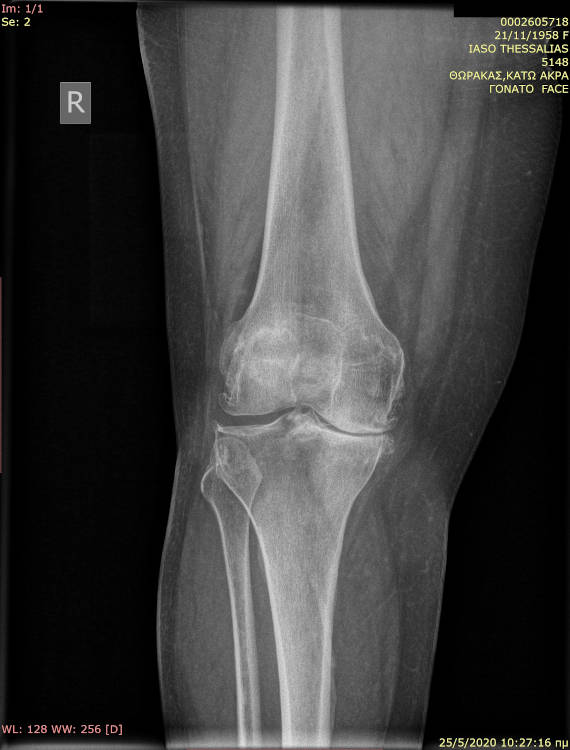

Η ομάδα της Β΄Ορθοπαιδικής κλινικής Ιασώ Θεσσαλίας, εκπαιδεύεται σε νέες τεχνικές χρήσης εξατομικευμένων προθέσεων στην ολική αρθροπλαστική γόνατος.

Πληροφορίες για την αντιμετώπιση της αρθρίτιδας γόνατος με ολική αρθροπλαστική μπορείτε να βρείτε εδώ